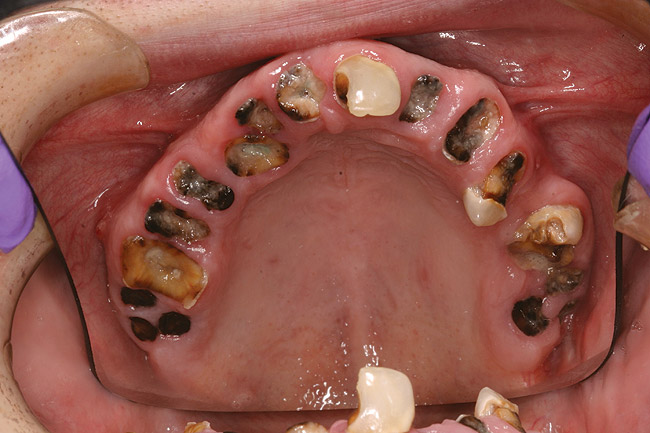

When smoked, methamphetamine produces highly toxic and corrosive fumes of lithium, muriatic, and sulfuric acids that can destroy enamel rapidly. With continued use, methamphetamine can produce severe, rampant caries, similar to early childhood caries. Patients have reported noticing changes in the appearance of tooth structure in as little as 3 months of use. The affected surfaces are the buccal and labial smooth surfaces, as well as the interproximal surfaces (Figure 1 through Figure 3). Because in the general population the vast majority of decay is found in the posterior molars, when someone presents with rampant anterior lesions it should be a red flag for methamphetamine use.5

Figure 2  DEVASTATING EFFECTS When smoked, methamphetamine produces highly toxic and corrosive fumes of lithium, muriatic, and sulfuric acids that can destroy enamel rapidly. With continued use, methamphetamine can produce severe, rampant caries. When someone presents with rampant anterior lesions it should be a red flag for methamphetamine use.

Figure 2

Figure 3  DEVASTATING EFFECTS When smoked, methamphetamine produces highly toxic and corrosive fumes of lithium, muriatic, and sulfuric acids that can destroy enamel rapidly. With continued use, methamphetamine can produce severe, rampant caries. When someone presents with rampant anterior lesions it should be a red flag for methamphetamine use.

Figure 3